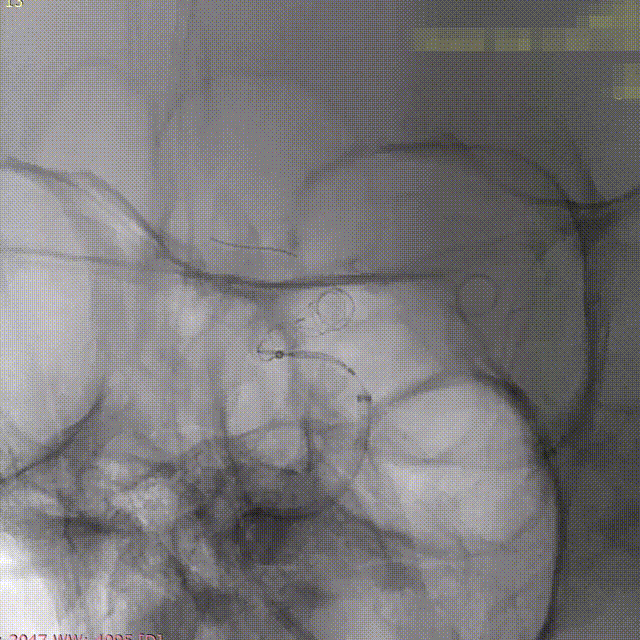

第二枚3*25支架沿017支架微导管上高。

第二枚支架远端释放。

第二枚支架释放至中段。

中段释放适当推挤系统,保持贴壁良好。

中段释放后造影。

继续释放支架。

继续释放支架,造影观察贴壁良好。

完全释放支架。

支架微导管沿推送导丝上高并将推送导丝撤出。

术后即刻造影。

术后重建。